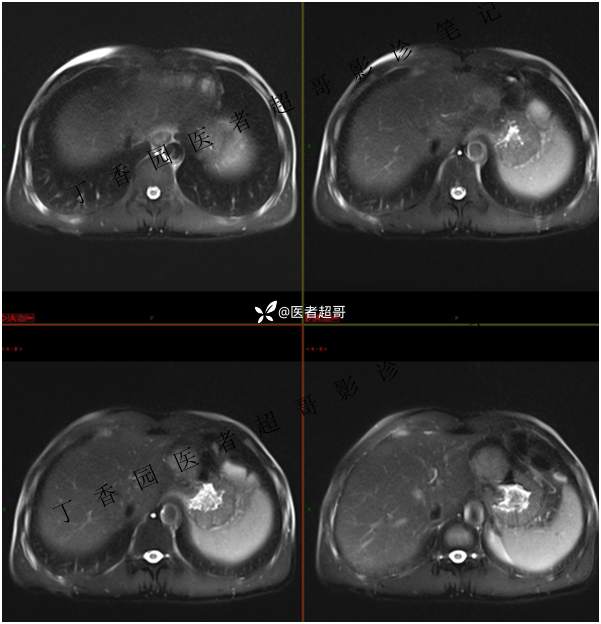

肝胃间隙肿瘤,间质瘤?平滑肌瘤?还是鞘瘤?有结果,请分析!

现病史:患者于3天前查体行肝胆脾胰肾彩超示肝内实性占位,无恶心、呕吐,无发热、寒战,无腹胀、腹泻,进一步于医院行上腹部CT增强示:肝胃交界处肿块。未行特殊治疗。今患者为求进一步治疗,来我院就诊,门诊以“肝占位性病变”收入院。患者自发病以来,神志清,精神可,饮食睡眠可,二便可,体重近期未见明显变化。